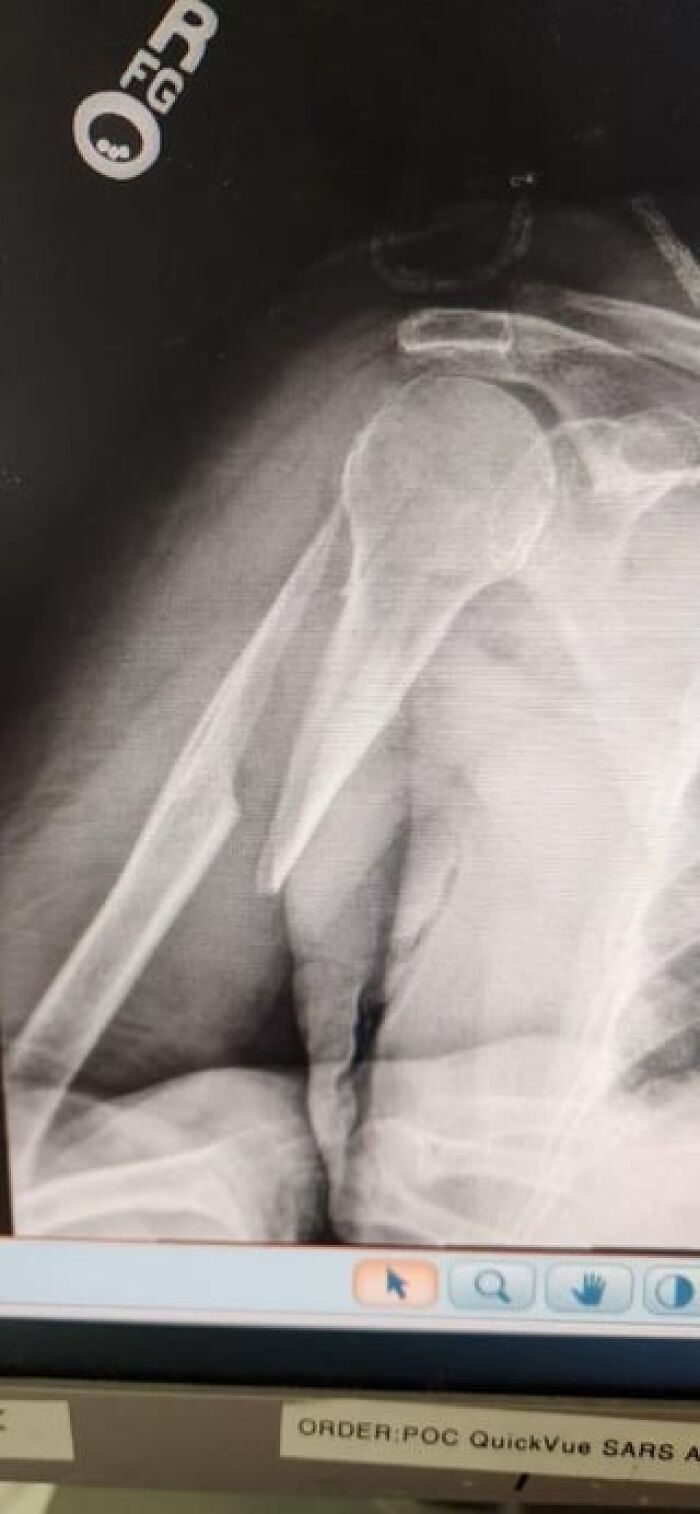

#36 92yo Grandmother With Massive Fracture: Docs Won’t Operate And Will Stop Giving Pain Meds

Image source: medical